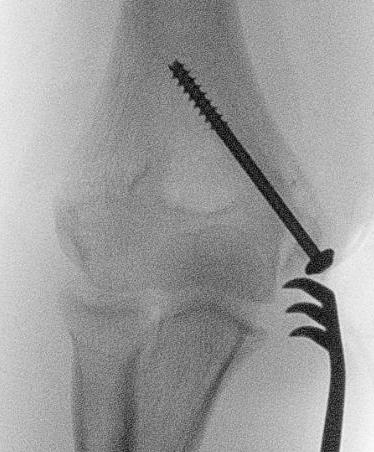

Displaced medial epicondyle fracture

![]()

Open reduction internal fixation

Technique

AO foundation medial approach to elbow

Youtube open fixation medial epicondyle video

Vumedi percutaneous fixation medial epicondyle video

Supine with arm table / consider patient prone to aid reduction

- medial incision

- find and protect ulna nerve

- reduce fragment anatomically

- ORIF with K wires or screw

- avoid olecranon fossa